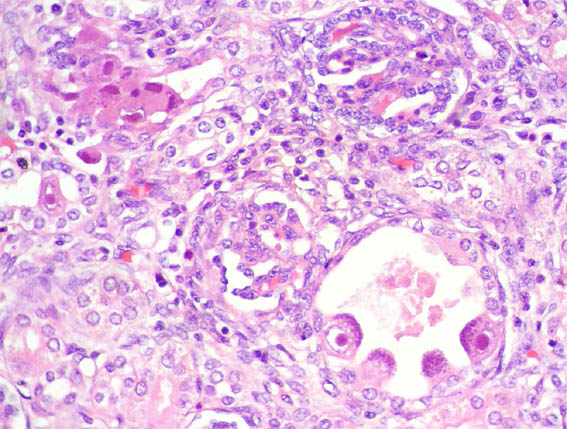

En ambos riñones fetales se observa lo mostrado en las siguientes imágenes.

Figura 4.

H&E, X400.